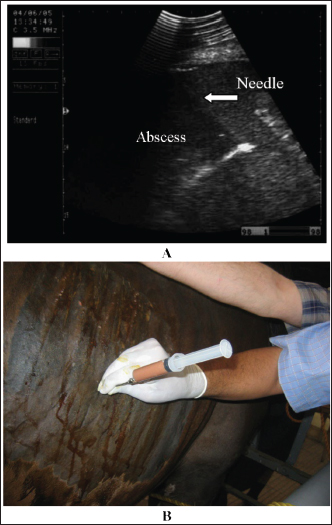

Abdominal abscess was strongly suspected on the basis of ultrasonographic findings (Fig. 20). The differential diagnoses include abdominal neoplasia. Ultrasonography is also useful for percutaneous needle aspiration for bacteriologic evaluation and facilitates intralesional antibiotic treatment and drainage because the thick abscess capsule prevents the spread of antibiotics (Tharwat et al., 2024c) (Figs. 21 and 22). For large abscesses, transcutaneous aspiration of pus should be performed under ultrasound guidance, as reported in cattle (Mohamed et al., 2002; Mohamed et al., 2003a,b,c; Mohamed and Oikawa, 2008). The ultrasound-guided percutaneous drainage of abdominal abscesses has several advantages. First, the animal should not be anesthetized. Second, surgery is not required, and consequently postoperative drawbacks will not develop. Third, percutaneous drainage is typically cost-effective. Fourth, percutaneous ultrasound-guided drainage can be performed promptly after diagnostic ultrasound is performed because the methodology does not require any particular planning or preparation and can be completed quickly if the examiner is experienced. Complications associated with ultrasound-guided percutaneous aspiration of the abscess in the present case were not encountered (Tharwat et al., 2024c). Follow-up after pus aspiration confirmed the treatment response, reduction in abscess size, and recovery (Figs. 23 and 24).

Fig. 20. Ultrasonograms of an 8-year-old Thoroughbred mare with abdominal abscess. Image A shows a sonogram obtained at admission (day 0) in which a mass with a thick echogenic capsule with homogenous and echogenic internal contents was identified. The mass was located close to the liver, deforming its right lobe margins B.

Fig. 21. Ultrasonograms of an 8-year-old Thoroughbred mare with abdominal abscess. Image A shows the fine-needle aspiration technique used to drain the content of the abscess. Image B an ultrasound-guided aspiration of pus from an abdominal abscess.